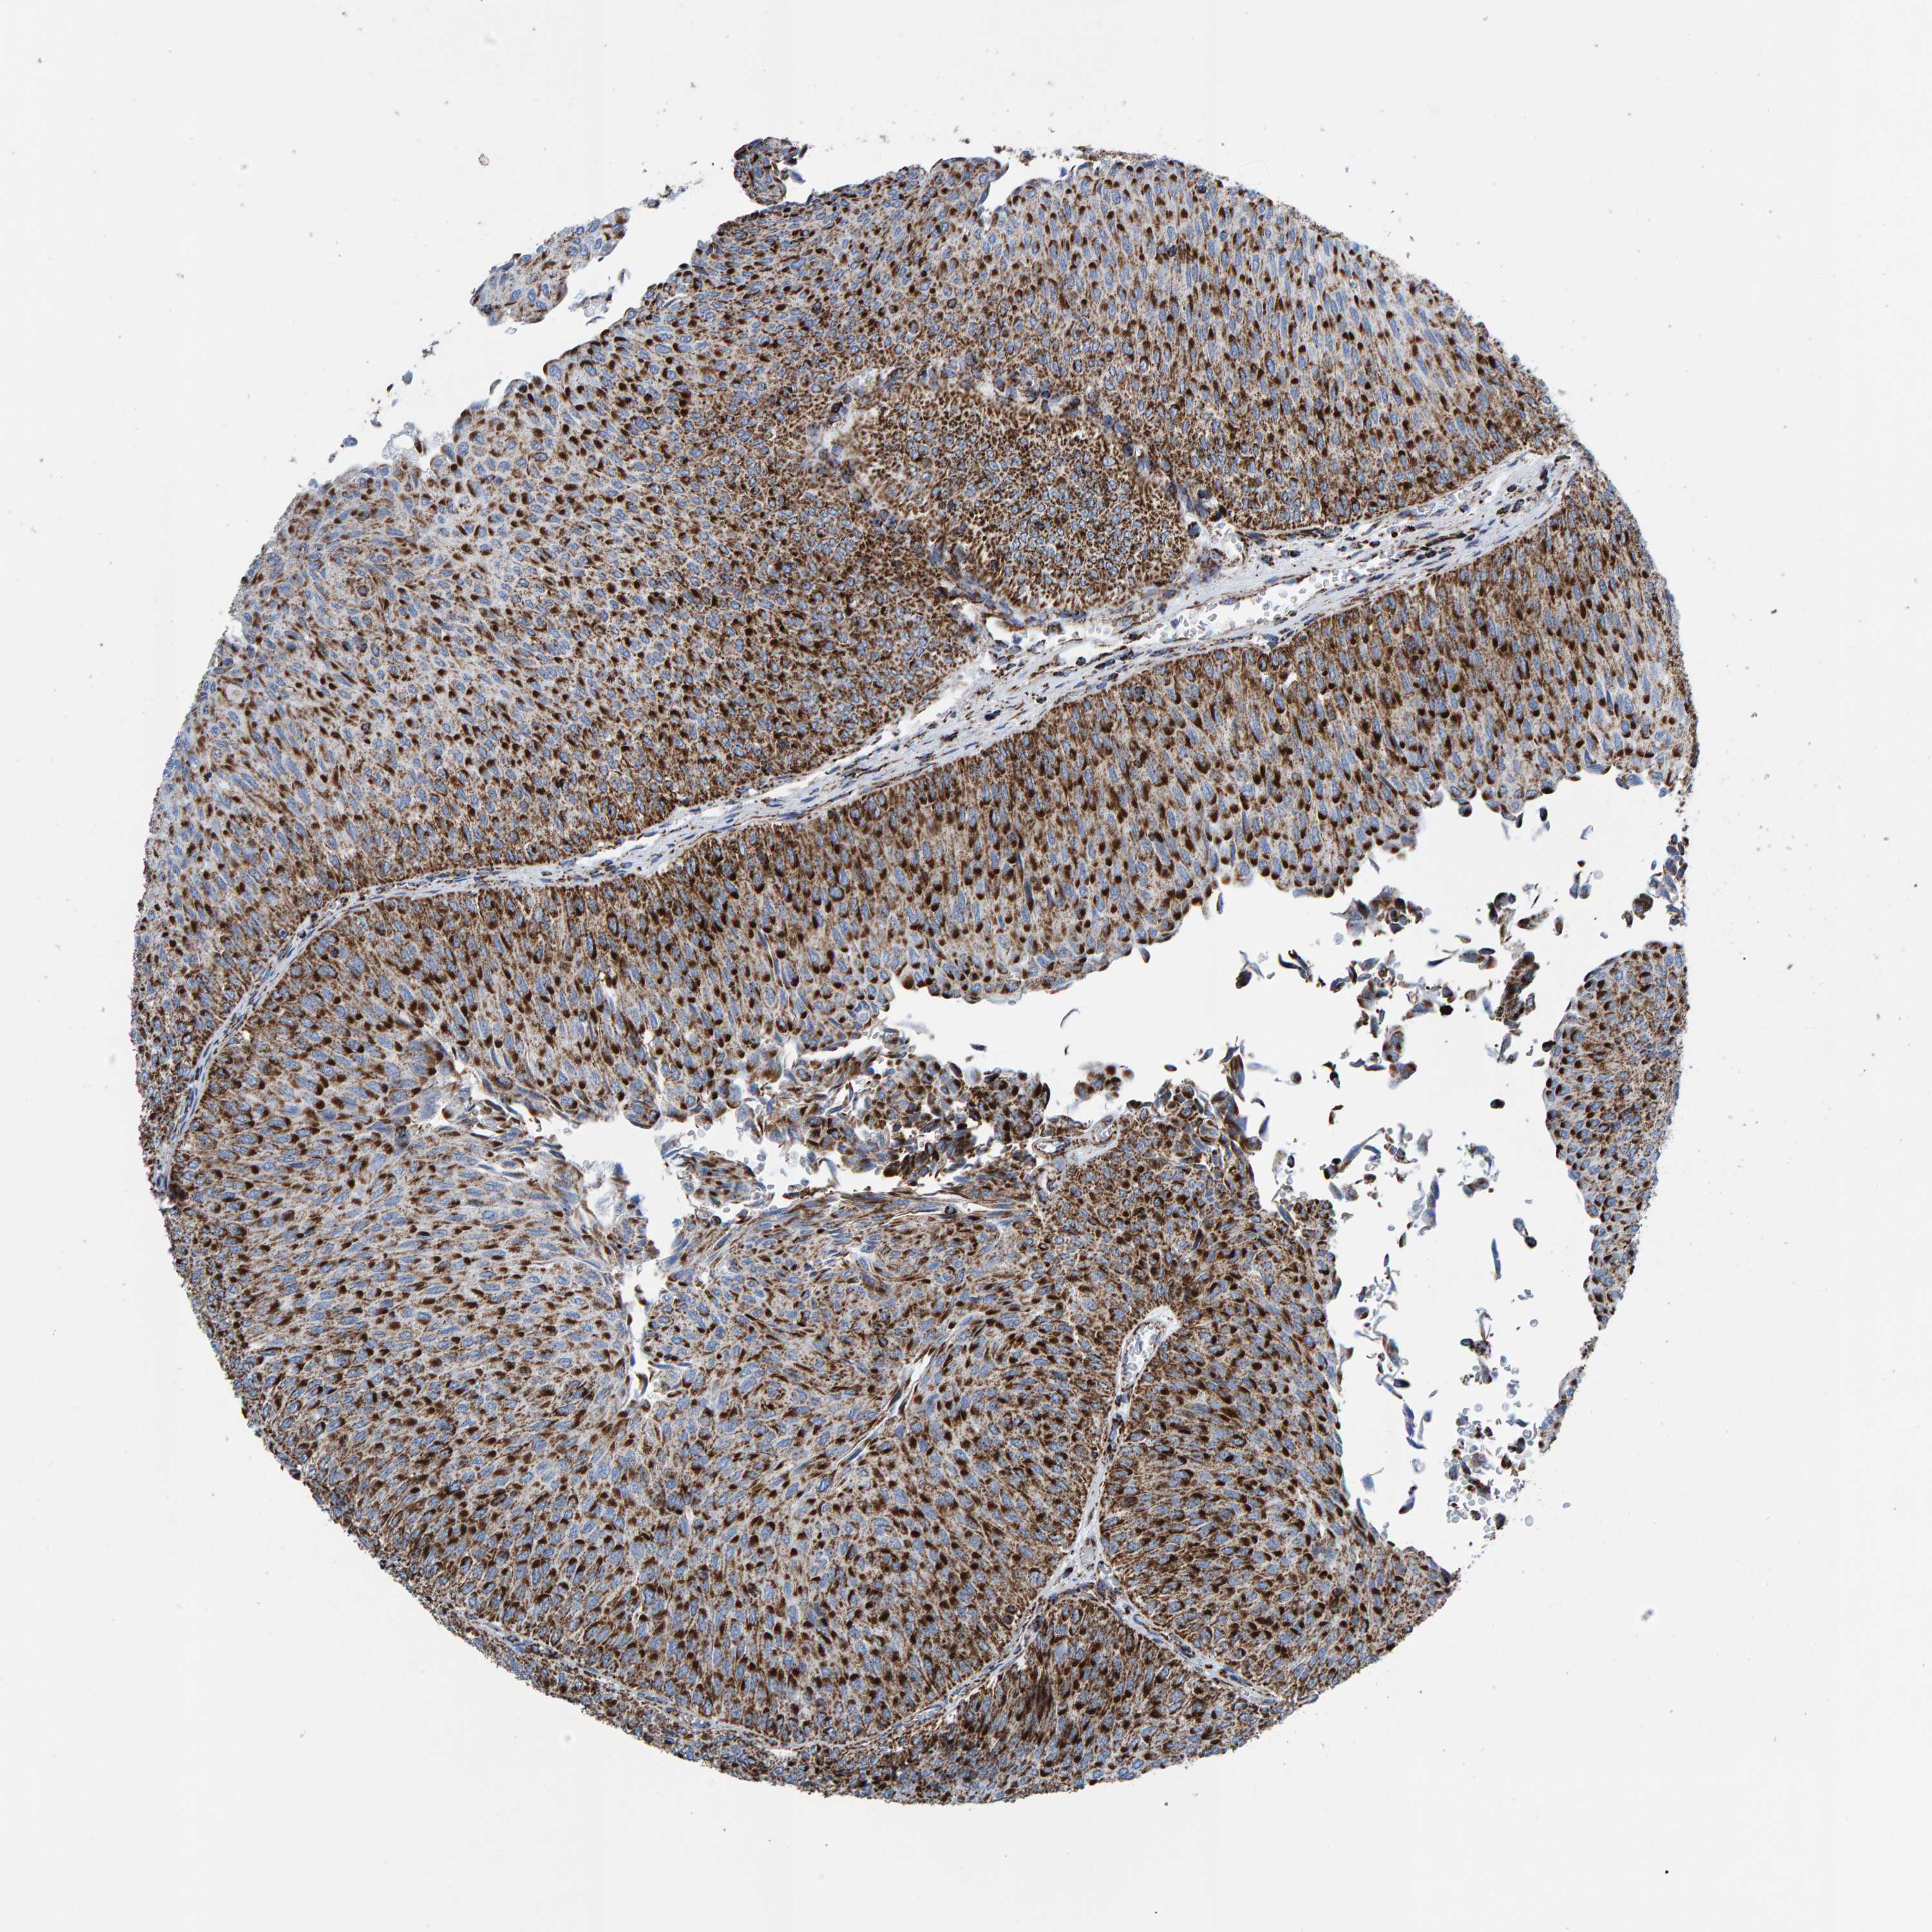

UROTHELIAL CANCER - Protein expressioni

A mouse-over function shows sample information and annotation data. Click on an image to view it in a full screen mode. Samples can be filtered based on level of antibody staining by selecting one or several of the following categories: high, medium, low and not detected. The assay and annotation is described here.

Note that samples used for immunohistochemistry by the Human Protein Atlas do not correspond to samples in the TCGA dataset.

Antibody stainingi

Antibody staining in the annotated cell types in the current human tissue is reported as not detected, low, medium, or high, based on conventional immunohistochemistry profiling in selected tissues. This score is based on the combination of the staining intensity and fraction of stained cells.

Each image is clickable and will lead to virtual microscopy that enables deeper exploration of all samples and also displays staining intensity scores, fraction scores and subcellular localization as well as patient and tissue information for each sample.

Antibody HPA022853

Antibody HPA023043

Antibody HPA023048

Staining

High

Medium

Low

Not detected

Intensity

Strong

Moderate

Weak

Negative

Quantity

>75%

75%-25%

<25%

None

Location

Nuclear

Cytoplasmic/membranous

Cytoplasmic/membranous,nuclear

Urothelial carcinoma, Low grade

Urothelial carcinoma, High grade